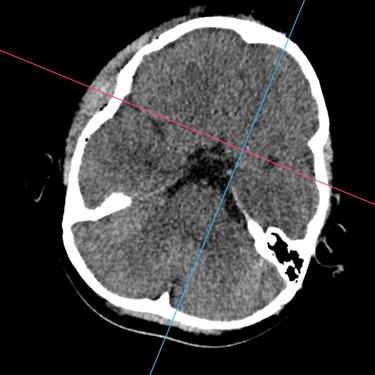

La fractura craneal es una lesión que puede producirse tras un traumatismo craneoencefálico, con riesgo de comprometer el cerebro y las estructuras intracraneales. Los síntomas incluyen dolor local, edema, hematomas y, en casos graves, alteración del nivel de conciencia. La tomografía computarizada (TC) es el estudio de elección para su diagnóstico, ya que permite identificar con precisión el trazo de fractura, desplazamientos óseos, hemorragias asociadas y la afectación de senos venosos o base de cráneo. Un diagnóstico temprano mediante TC es esencial para definir la conducta terapéutica y prevenir complicaciones neurológicas potencialmente graves.